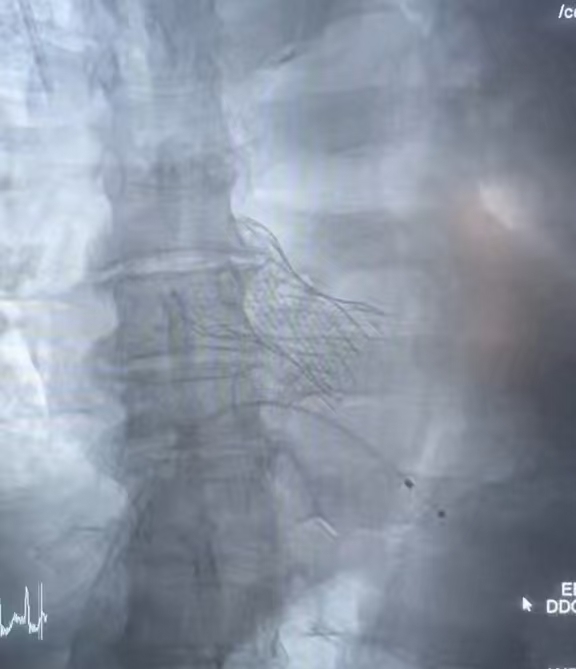

手术当天,在麻醉科姚俊岩主任团队精准护航下,何奔主任、江立生副主任医师、王建主治医师组成的介入团队,从外周血管准备,跨瓣,预扩张到瓣膜支架。没有大开胸,仅通过大腿根部的血管通路,导丝如灵蛇般穿越严重狭窄的瓣膜口,球囊精准扩开狭窄的“大门”,一枚崭新的生物瓣膜支架被稳稳释放到主动脉窦,完美取代了那扇“锈死”的阀门。整个过程行云流水,用时不到一小时!实时监测屏幕上显示:主动脉跨瓣压差从术前的100mmHg降至0mmHg!且瓣膜工作完美,没有任何反流,成功为老人心脏打开了“生命通道”。

生物瓣膜支架植入后,主动脉跨瓣压差即刻降至0mmHg,血压因瓣膜狭窄的解除迅速飙升

生物瓣膜支架顺利植入